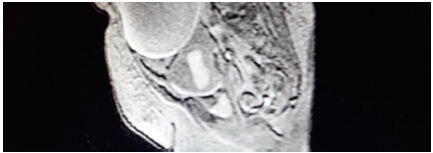

El informe de la RM abdominopélvica con gadolinio iv (cortes axiales Spin Echo-SE potenciados en T1 y Fast Spin Echo potenciados en T2 sin gadolinio y cortes axiales SE potenciados en T1 con gadolinio) revela una voluminosa imagen quística multitabicada con nódulos murales, que ocupa casi la práctica totalidad del hemiabdomen izquierdo llegando a pelvis menor (fig. 1 y 2). No se aprecia realce de la lesión tras la inyección de contraste ni tampoco imagen clara de núcleo sólido. La lesión es sugestiva de cistoadenocarcinoma de ovario izquierdo. Se aprecia contenido hematometra en cavidad uterina.